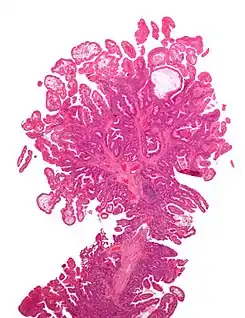

El síndrome de Peutz-Jeghers es una enfermedad autosómica dominante, se caracteriza por la producción y la presencia de pigmentaciones epidérmicas, además de la presencia de hamartomas gastrointestinales; este hecho fue confirmado en 1987 por Giardello, el cual, reporto 31 casos de síndrome de Peutz-Jeghers, con daño gastrointestinal asociado a hamartomas. [1]

Generalmente la presencia de estos síntomas como los hamartomas no se considera perjudicial o maligna, pero, en el síndrome de Peutz-Jeghers varios autores han reportado casos con excesivo daño gastrointestinal. La presencia de las pigmentaciones suele ocurrir por el desplazamiento epitelial debajo de la capa muscular. [1]

No existe una presentación típica del síndrome de Peutz-Jeghers,[3] sin embargo, en algunos pacientes suele predominar las hiper pigmentaciones muco-cutáneas acompañados de pólipos intestinales que a su vez desencadenan cólicos gastro intestinales de moderada o severa intensidad, los mismos causan rectorragia ya sea esta oscura (melenas) o clara (hematoquecia).[5]